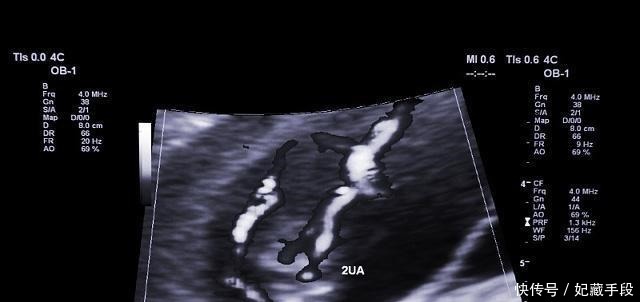

孕期,肚子一跳一跳的是怎么回事?或许很多人以为是胎动!胎儿的胎动一般都是有规律性的,但是有时候孕妈妈也会感觉到自己的肚子一跳一跳的,而且也具有一定的规律性,其实这种情况不是简单的胎动,也不是宝宝的心跳,而是胎儿在孕妈妈的肚子里打嗝。

为什么胎儿会打嗝?我们都知道胎儿在孕妈妈的肚子里生长发育,不会自己张口吃饭也不需要呼吸胎儿,主要是通过脐带从妈妈的身体里获取氧气和营养的,但是等到胎儿发育到第28周左右的时候就会练习吞咽,这个动作,有时候就可能一不小心给呛到了羊水,刺激到宝宝横膈膜,这时候宝宝就会出现打嗝的症状。

其实有一些孕妇可能感觉如果宝宝在肚子里面经常打嗝的时候是自己吃的东西太多了,所以让宝宝营养过剩才会出现这样的情况,其实是宝宝的肺部发育的一个现象,通过这样的方法可以锻炼宝宝的吞咽能力,尤其是宝宝的肺部功能可能会得到提升,所以说如果大家感觉到自己的肚子老是一跳一跳的,那么很可能是宝宝在为出生之后的正常呼吸做准备,所以说大家不必紧张。